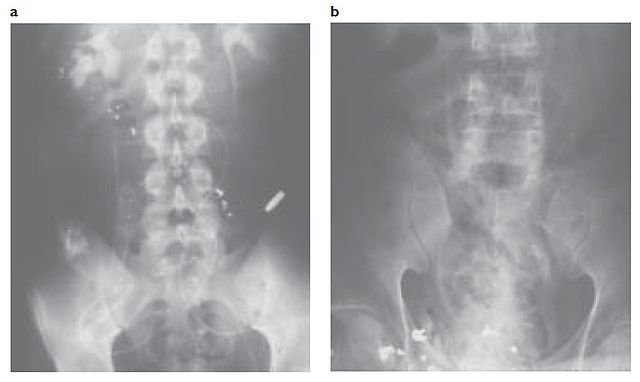

English: Fig. 1-5 (a) The casualty sustained a gunshot wound to the abdomen; this radiograph (b) shows multiple fragments and the retained core from an AK-47 round. The casualty’s injury to the upper urethra was treated with repair and insertion of a stent.

book published in 2005, x-rays made during the Vietnam War era |

Urology In The Vietnam War: Casualty Management and Lessons Learned, online at: https://ke.army.mil/bordeninstitute/other_pub/urology/Urol1.pdf |